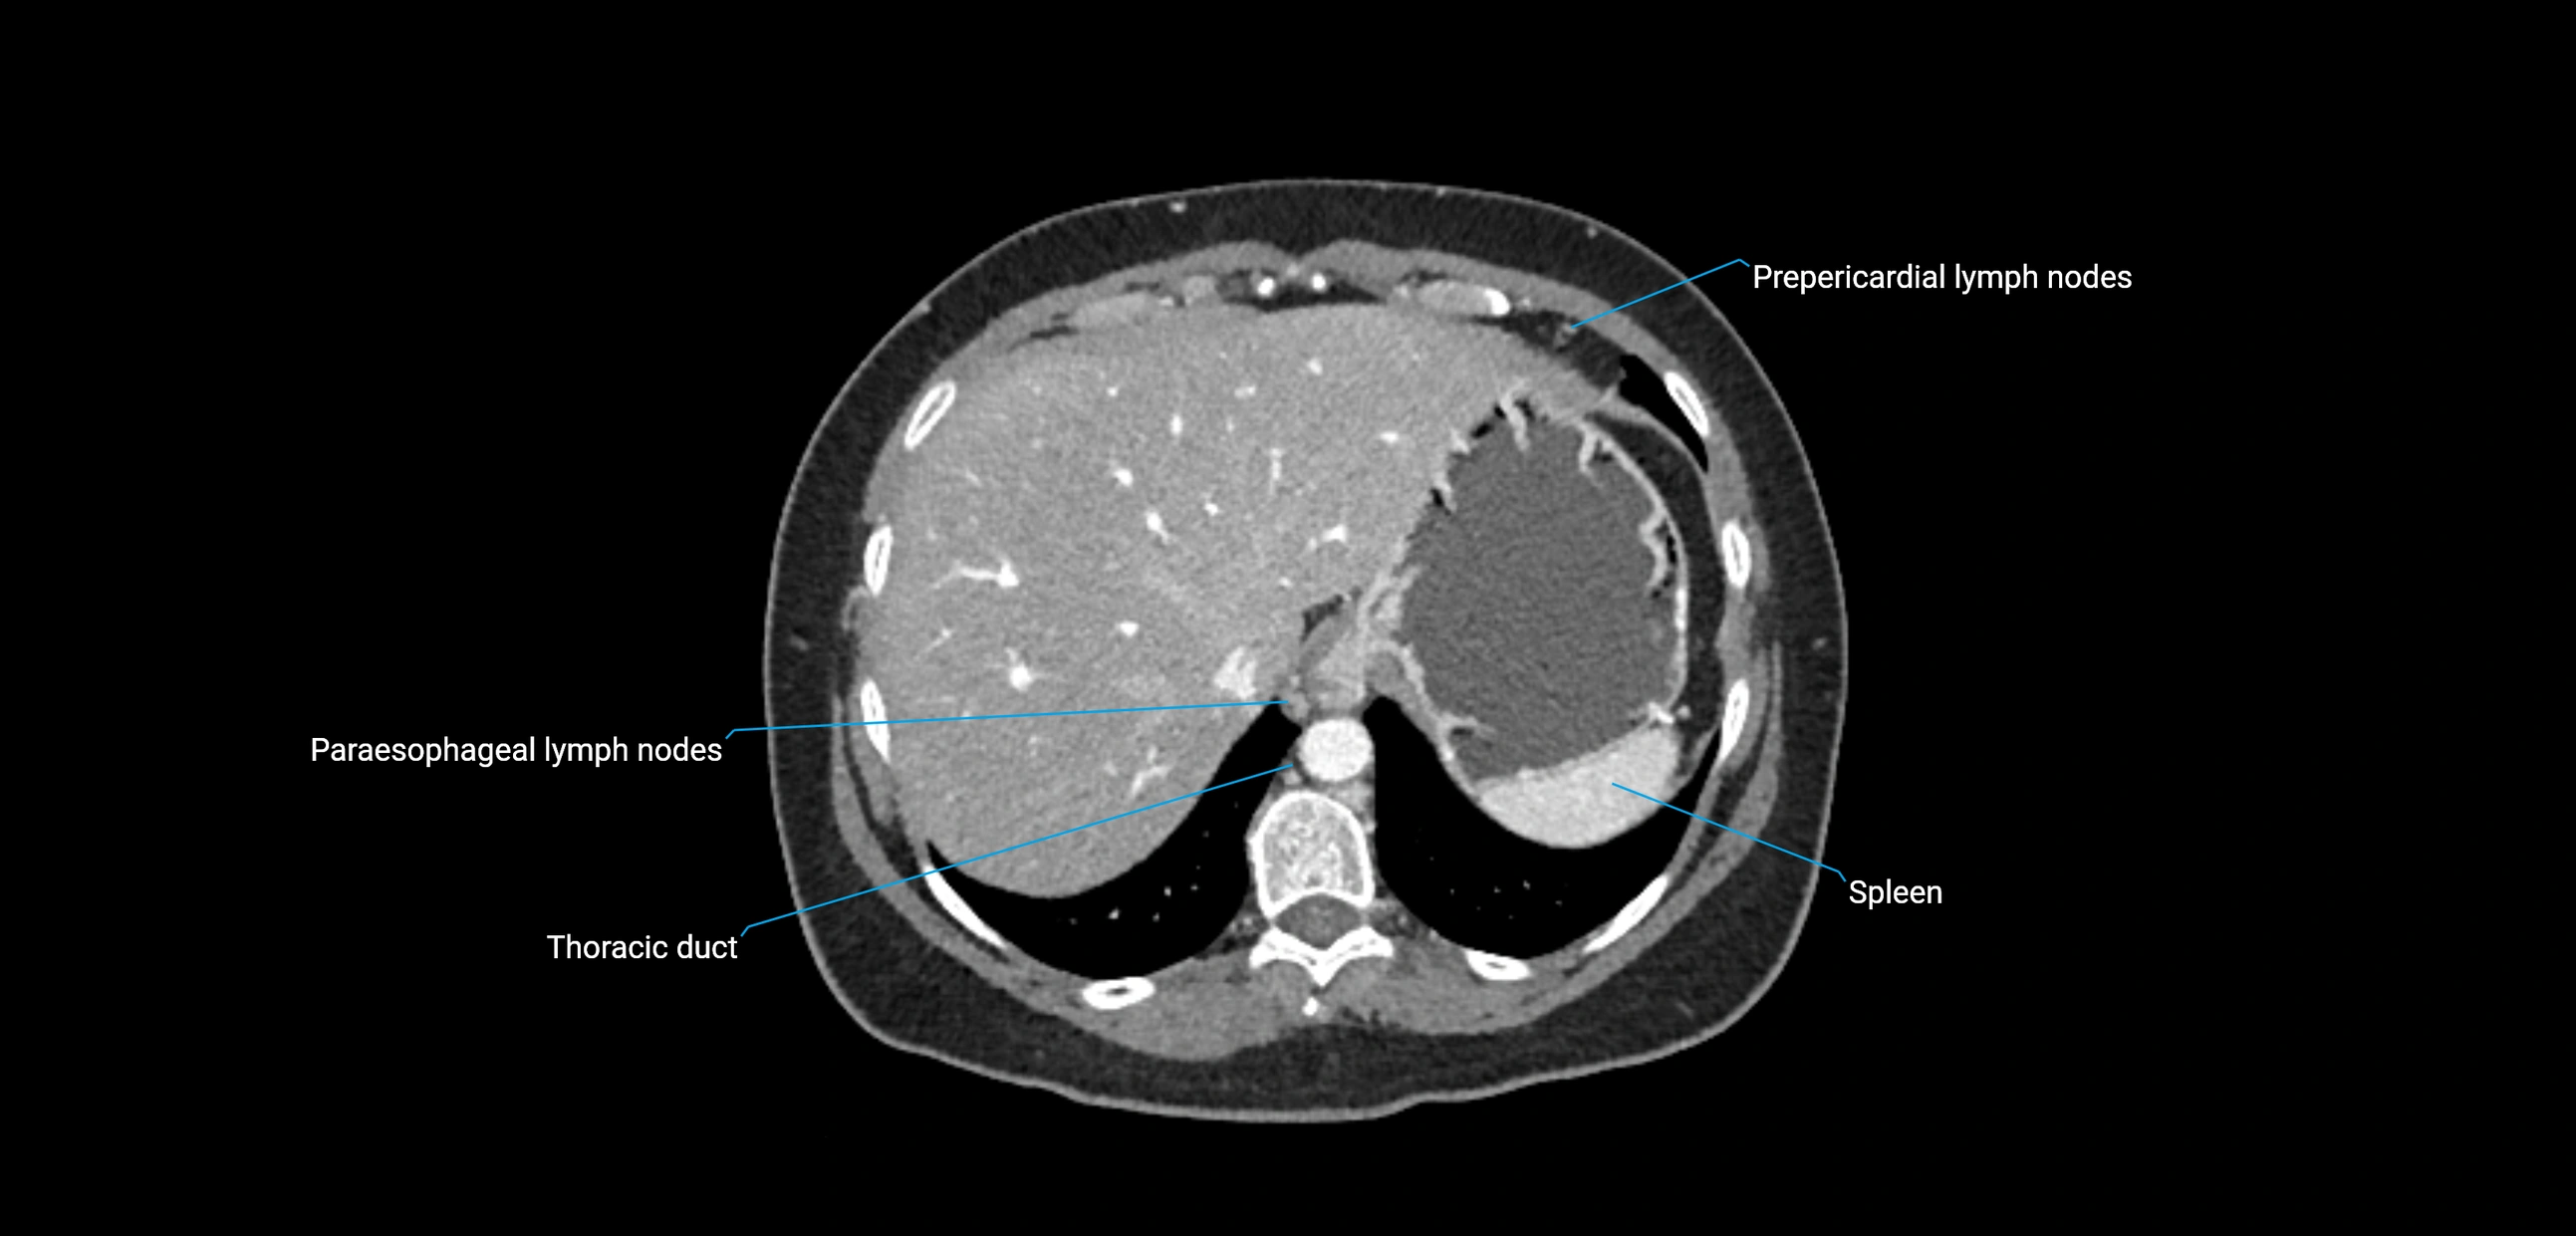

CT image

image